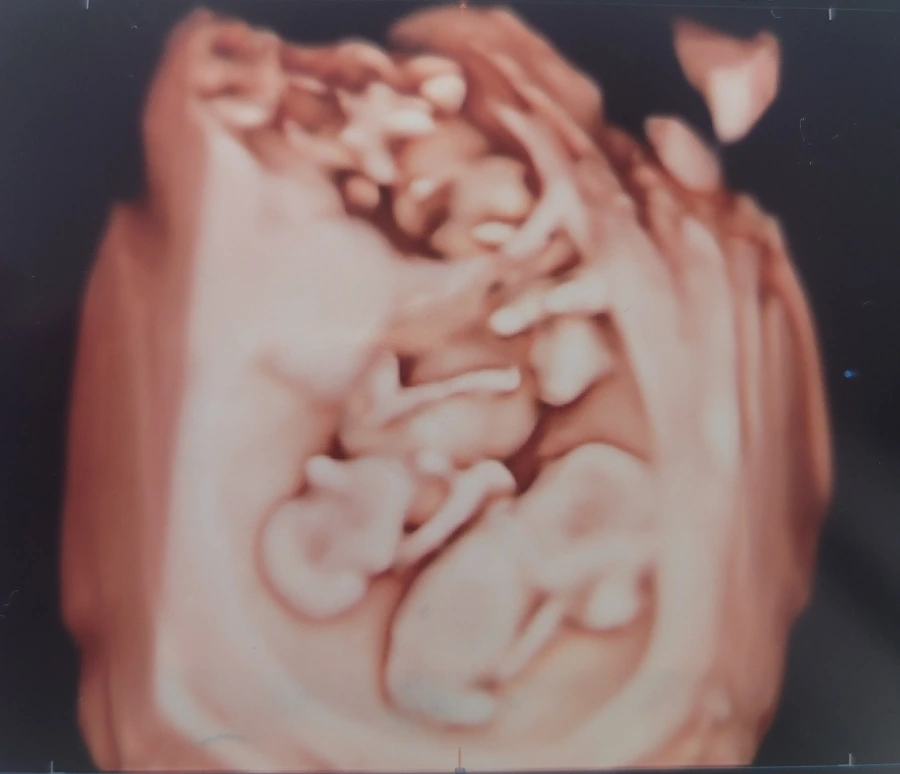

아기 하나하나 자세하게 보고, 단태아라면 엄빠 닮은 입체초음파 사진을 받기도 하는 정밀 초음파는 정밀이라는 이름에 맞게 검사 시간이 꽤 걸린다. 정확히 기억나진 않지만 대략 40분~1시간은 걸린 것 같다. 뱃살 때문에 안그래도 뱃속이 좁을 것 같은데 셋이서 같이 쓰고 있으니 오죽할까. 옹기종기 모여있는 삼둥이의 모습을 정밀하게 보느라고 시간이 오래 걸릴 수 밖에 없었다. 더 잘 보기 위해서 자세를 이쪽저쪽으로 바꾸기도 하면서 꼼꼼히 검사해줬고, 다행히 육안으로 보이는 큰 문제는 없었다. 매번 병원 가는날은 걱정이 가장 큰 날이기도 하고 안심도 가장 큰 날이 된다. 병원에 가기 전까지는 잘 있을까? 조그만 변화나 증상에도 걱정이 되고, 입덧이 힘들긴해도 입덧이 있으면 그래도 아기들이 잘 있다는 뜻일테니 한편으론 다행이라고 생각하면서 간접적으로 아기들의 존재를 느끼는것으로 마음을 달래는데, 병원에서 초음파 화면으로 깜빡이는 심장 세개를 보고나면, 그리고 일정한 모양으로 그려지는 맥박의 파동을 보고나면, 비로소 안심이라는걸 하게된다. 그래봐야 집에 가는 발걸음에 다시 걱정이 되긴 하지만.

혼돈의 입체 초음파